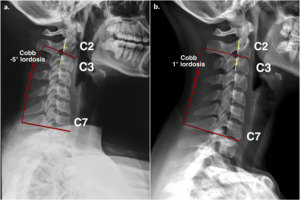

Myofascial trigger point palpation was performed for the cervical paraspinal, upper trapezius, rhomboid, suboccipital, and shoulder girdle muscles. Firm pressure on the cervical paraspinal and suboccipital trigger points produced a painful sensation over the back of the head. Trigger points in the trapezius, rhomboids, and shoulder girdle muscles caused only local discomfort. Sensory test results were within the normal limits for the upper extremities. Standing radiographs of the patient’s neck demonstrated reversed physiological cervical lordosis, with no noticeable bony degenerative changes (fig.1a).

The patient continued maintenance care after her complaints were resolved, with a frequency of once per week to once per month. Reassessment of patient symptoms, cervical ROM, neurological and orthopaedic findings, and radiographic reassessments was conducted in the 9th month after the initial visit. The cervical ROM and orthopedic examination were normal. Mild muscle tightness was occasionally noted after prolonged computer use; however, the patient reported no numbness in her arms or neck pain. There are no reduced muscle strength and deep tendon reflexes noted. Spurling tests, Upper limb tension tests, cervical distraction test and cervical rotation ROM test are all negative, suggesting the resolution of cervical nerve root irritation. A standing radiographic study was conducted for pre- and post-treatment comparisons and demonstrated an improvement in the physiological cervical lordosis (Figure 1a and 1b).

Our report supports the use of chiropractic care to manage reduced cervical lordosis and radiculopathy. The improvement in cervical lordosis after chiropractic care was evidenced on radiographs (fig.1b) upon reassessment; other studies supported our results.29,30 Moreover, the elimination of upper extremity numbness in the patient by her fifth visit also highlighted the value of cooperative chiropractic treatment for cervical radiculopathy. The concurrent nature of both changes indicates a plausible biomechanical mechanism between increased nerve tension in the cervical spine and reduced lordosis; other studies have reported similar findings.15,16,30